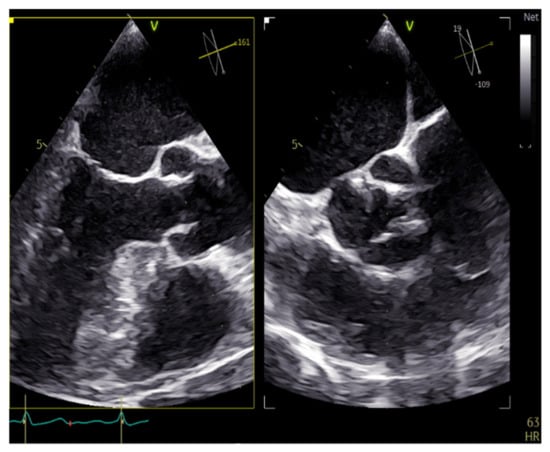

Figure 9. CMR image 4CH view of the heart.

Applsci 11 10549 g009

Figure 10. CMR image 2CH view.

4. Cardiac Magnetic Resonance (CMR)

4.1. T1-T2–LGE

One of the main advantages of CMR over other imaging techniques relies on myocardial tissue characterization. T1-weighted sequences are very useful to visualize cardiac anatomy in great detail and detect the presence of intra-myocardial fat. T1 mapping can also quantify myocardial fibrosis [16]. For the detection of myocardial edema, the best modality is the use of T2-weighted imaging. Additionally, the use of contrast agents such as gadolinium can significantly increase the diagnostic capacities of CMR (Figure 9 and Figure 10). Late gadolinium enhancement (LGE) is a useful tool for the proper identification of infarcted myocardium. This technique is mainly used along with perfusion CMR to assess whether a wall region in question is ischemic or infarcted (scar) [17,18].